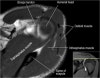

- Axial section

1) Anterior & posterior labrum

2) Subscapularis muscle & tendon

3) Biceps long head tendon

4) GH joint cartilage

5) Osseous structure

6) 관절액 있을때 FSE T2 FS에서 Labrum 선명, 관절액 없을때 FSE PD FS에서 Labrum 선명